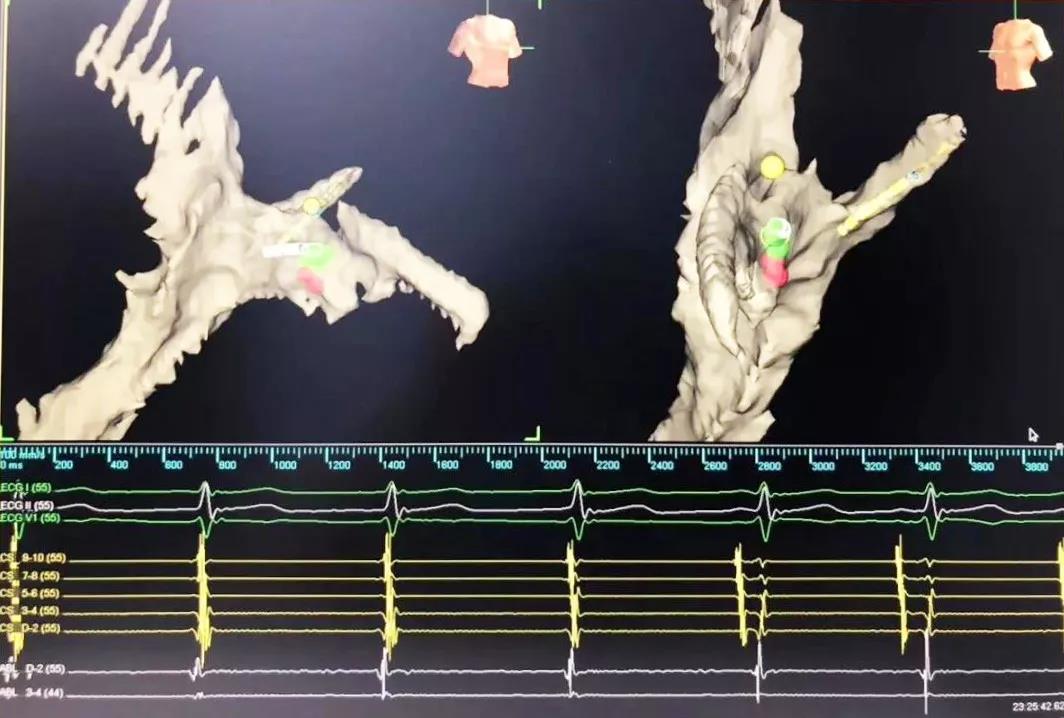

又一道難題擺在眼前,常規(guī)手術(shù)需要在X射線下進行,X射線會導(dǎo)致胎兒發(fā)育畸形。在心臟病醫(yī)院院長王海昌的帶領(lǐng)下,專家團隊仔細(xì)研究后,決定為張女士施行三維標(biāo)測系統(tǒng)指引下零射線心臟電生理檢查及射頻消融術(shù)。

在完成常規(guī)檢查,排除新型冠狀病毒肺炎的可能后,217日,由廉誠主刀,在三維標(biāo)測系統(tǒng)指引下行零射線心臟電生理檢查及射頻消融術(shù)。術(shù)中明確患者心動過速為房室結(jié)折返性心動過速,遂行房室結(jié)慢徑改良,消融完畢后反復(fù)刺激驗證,心動過速均不能誘發(fā),手術(shù)成功,歷時約1小時,全程零射線完成。這也是西安國際醫(yī)學(xué)中心醫(yī)院心臟病醫(yī)院的首例零射線治療特殊人群心律失常病例。